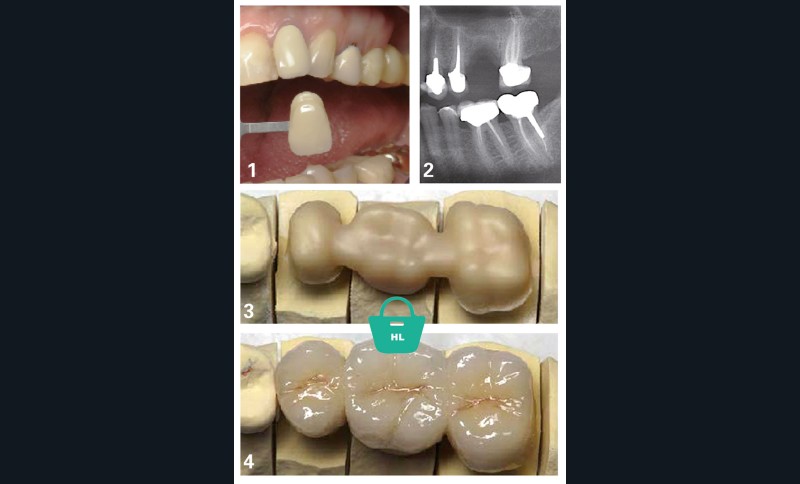

Dans le cas exposé figures 1 à 4, le traitement prothétique proposé pour remplacer la 26 peut être la couronne sur implant (avec sinus-lift) ou le bridge traditionnel 25-[26]-27.

La patiente écarte d’emblée le sinus-lift et préfère le bridge traditionnel, les futurs piliers ayant déjà des coiffes prothétiques.

Quel bridge lui proposer alors ?

La situation clinique apporte souvent une réponse claire. Ici, il paraît indispensable de proposer une solution esthétiquement acceptable, comparable aux coiffes céramo-métalliques déjà présentes sur les dents piliers. On peut, bien sûr, à partir du 1er janvier 2020, évoquer une solution RAC-0 dans pareille situation, c’est-à-dire un bridge métallique ! Mais le contexte clinique s’impose et s’oppose à une telle alternative.

Ainsi, en pratique (tableau 1) :

– jusqu’au 1er janvier 2020, les honoraires du traitement prothétique par bridge sont fixés librement, avec tact et mesure, au moyen d’un devis préalablement établi ;

– au 1er janvier 2020, on peut évoquer le bridge métallique RAC-0 à titre d’information, mais cette solution n’est pas envisageable dans ce contexte clinique ;

– au 1er janvier 2021, le bridge céramo-métallique pour remplacer une dent autre qu’une incisive entre dans le panier RAC-M. Le bridge céramo-céramique reste dans le panier HL.